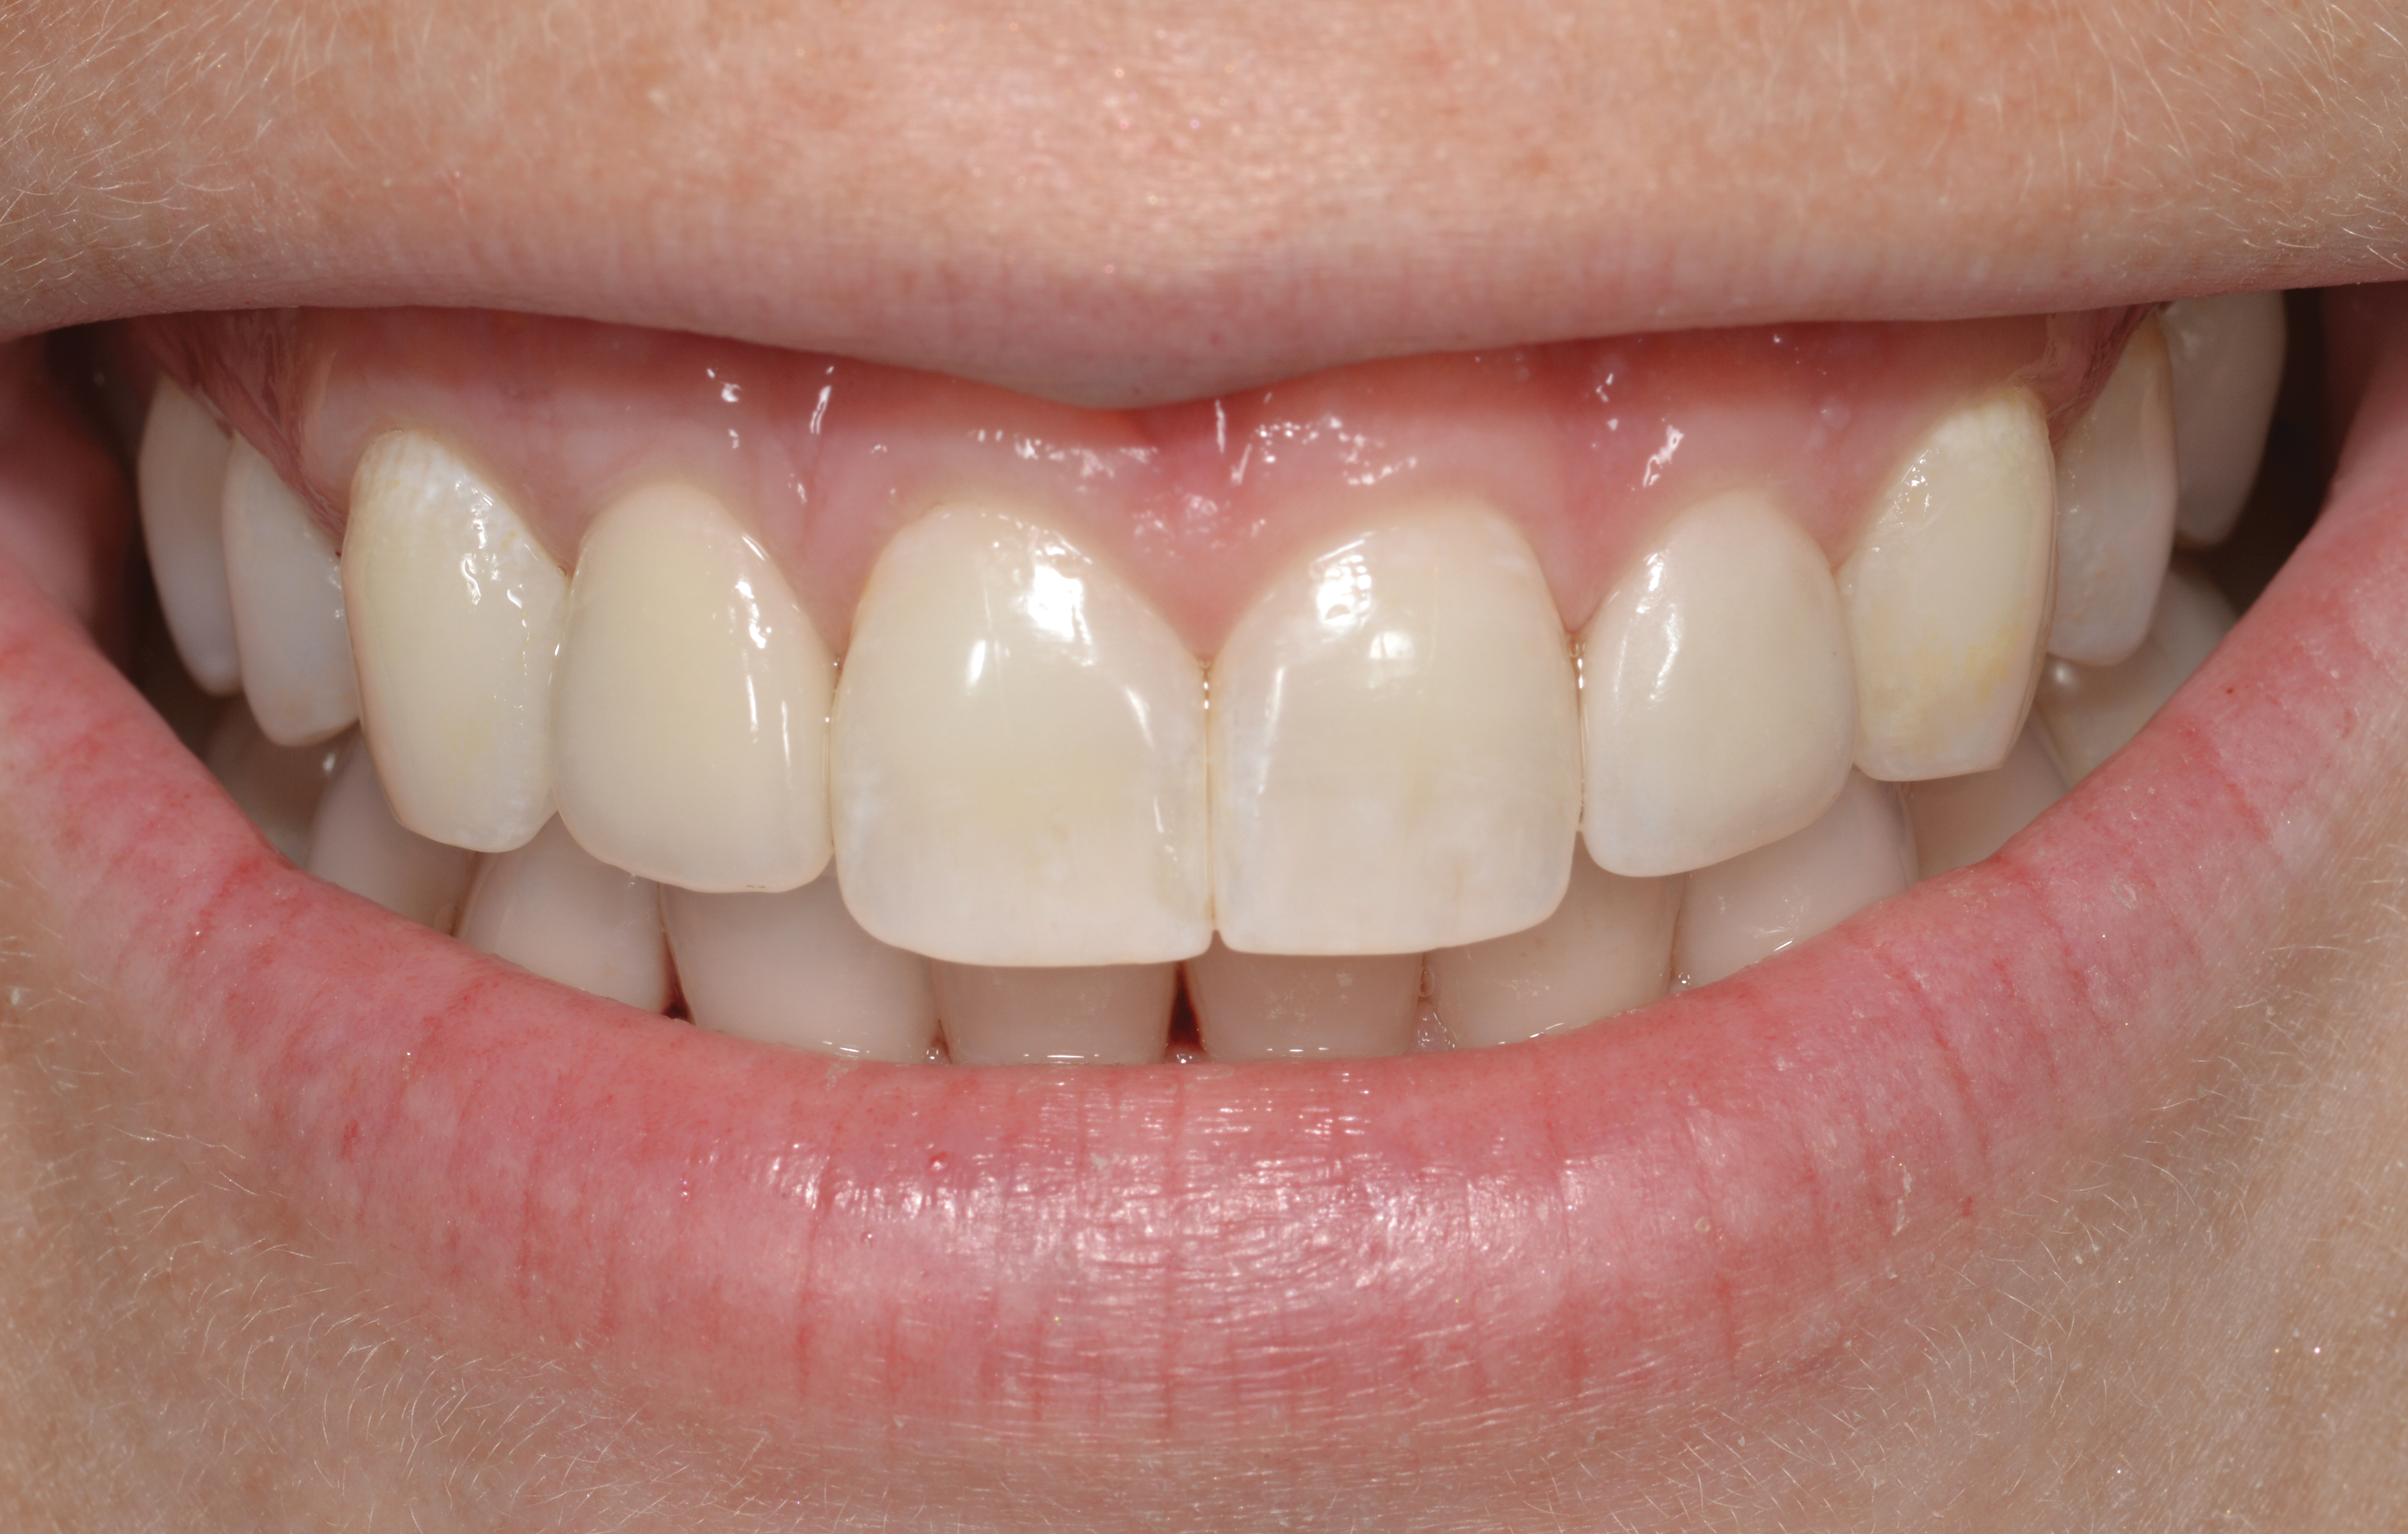

Fig 14. The extraoral smile view of the esthetically satisfied patient at 4 years recall.

Figure 14